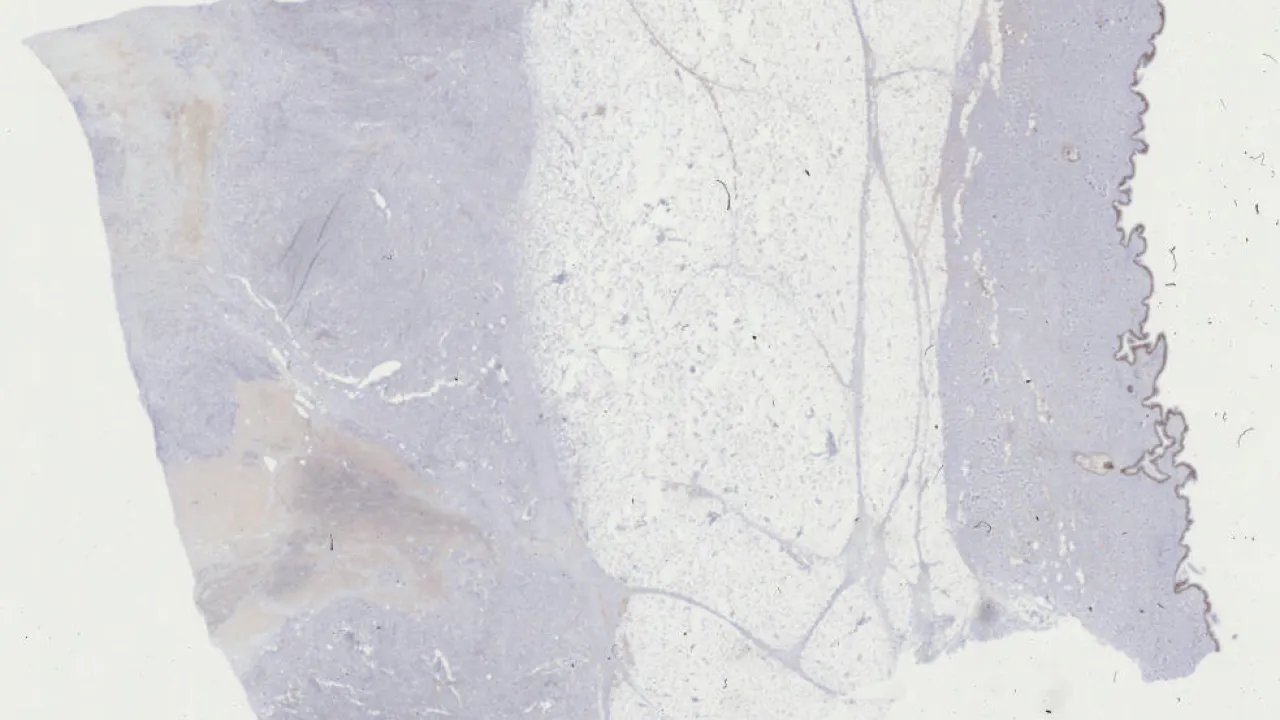

Breast, Epithelial-myoepithelial invasive carcinoma, p63 stain